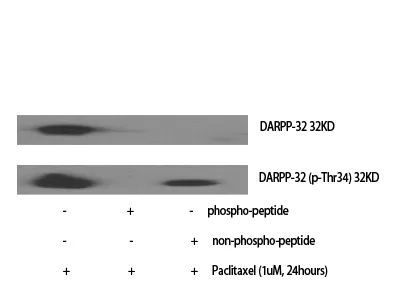

DARPP-32 Rabbit Polyclonal Antibody

Cat: APRab09793

Size1:50μl Price1:$118

Size2:100μl Price2:$220

Size3:500μl Price3:$980

Size2:100μl Price2:$220

Size3:500μl Price3:$980